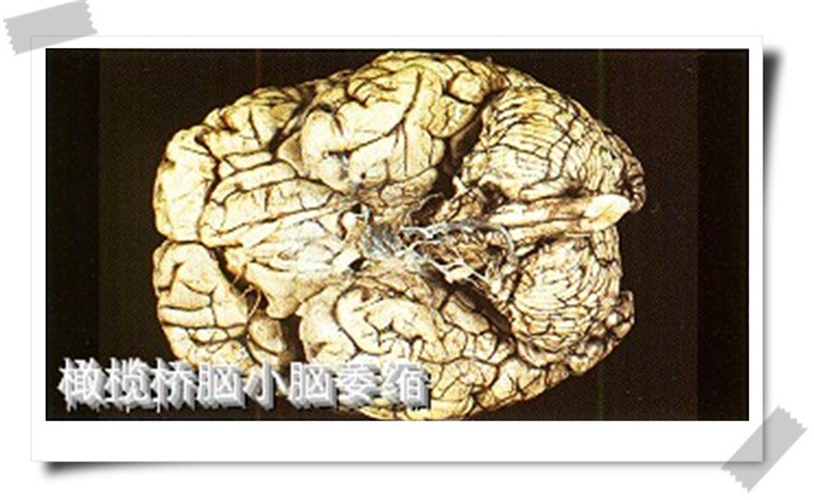

橄欖橋腦腦萎縮

橄欖橋腦小腦腦萎縮